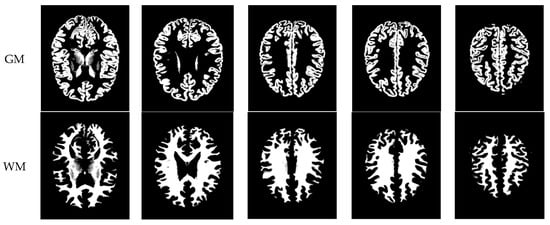

As mentioned before, the images of the first five datasets in Table 3 were used to evaluate the performance of the HMRF-WOA. Figure 1, Figure 2, Figure 3, Figure 4 and Figure 5 show some slices of a T1-weighted image (slices: 84, 95, 105, 108, 120). These brain images correspond to the slices under different types of conditions, such as database type, dimension image, noise level, intensity non-uniformity level, and slice thickness (mm). In Table 1, rows 1 to 5 summarize the parameters of Figure 1, Figure 2, Figure 3, Figure 4 and Figure 5, respectively. Figure 6 represents the ground truth segmentation of slices 84, 95, 105, 108, and 120. In this figure, each column contains the three tissues, GM, WM, and CSF, of each slice. Figure 7, Figure 8, Figure 9, Figure 10 and Figure 11 show the segmentation results, where the four tissues (BG, GM, WM, and CSF) are shown with different colors. The yellow, red, and green colors represent the segmented regions of GM, WM, and CSF, respectively. As we can also see from these figures, the resulting segmented images in Figure 7, Figure 8, Figure 9, Figure 10 and Figure 11 are almost close to the initial images in Figure 1, Figure 2, Figure 3, Figure 4 and Figure 5.

The qualitative analysis provides a visual representation of the segmentation approaches. The visual comparison of the resulting images using the HMRF-WOA appears to be more similar to the reference image (ground truth), where Figure 1, Figure 2, Figure 3, Figure 4 and Figure 5 show the GM, WM, and CSF tissue regions of the reference image with higher values of noise levels (3, 5, 7, and 9%) and intensity non-uniformity levels (20, 40%), whereas Figure 7, Figure 8, Figure 9, Figure 10 and Figure 11 show the subject images obtained using the proposed technique. However, this result shows that with higher values of noise and intensity non-uniformity, the algorithm, with its hyperparameters, is able to segment the tissue regions correctly.

Figure 6. Ground truth segmentation of the GM, WM, and CSF tissues.